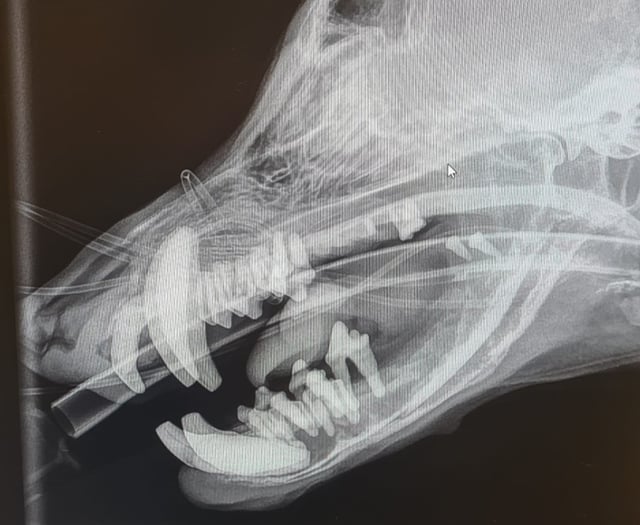

Barry's 'Rubber Jaw' Treated at South Moor